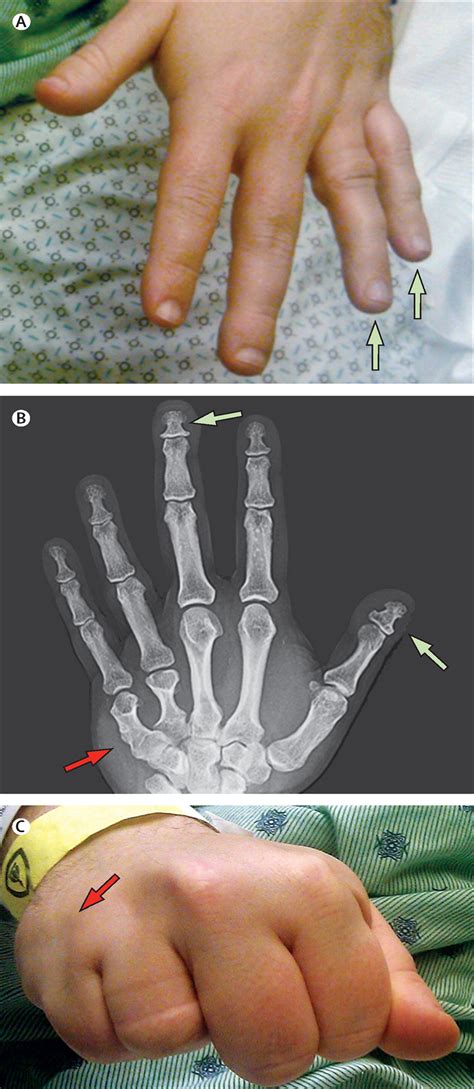

• Brachydactyly: Shortening of the bones in the hands and feet, particularly the fourth and fifth metacarpals and metatarsals.

• Subcutaneous Ossifications: These are small, hard lumps of bone that form under the skin, often in the hands, feet, and other areas.

• Clinical Evaluation: A thorough physical examination to assess the characteristic features of AHO, such as short stature, obesity, and brachydactyly.

• Orthopedic Interventions: Surgical procedures may be required to correct skeletal abnormalities, such as brachydactyly or subcutaneous ossifications.